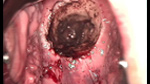

婦科leep錐切手術 CIN2-3

• CIN 2-3CIN 2-3